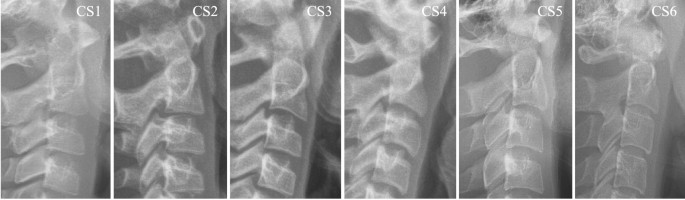

Images of CVM stages based on Baccetti’s classification method (CS1–CS6). Cervical vertebral maturation stages based on Baccetti’s classification method. Lateral cephalometric radiographs illustrating the six stages of cervical vertebral development: CS1-CS6 showing progressive morphological changes in C2-C4 vertebral bodies, including concavity development at inferior borders and overall vertebral shape modifications used for skeletal maturity assessment.

Cervical Vertebral Maturation (CVM Stage): As shown in Figure 2, CVM staging followed Baccetti’s six-stage method25, evaluating morphological characteristics of C2–C4 vertebral bodies, including concavity presence, depth, and extent at inferior borders, and overall vertebral shape modifications.